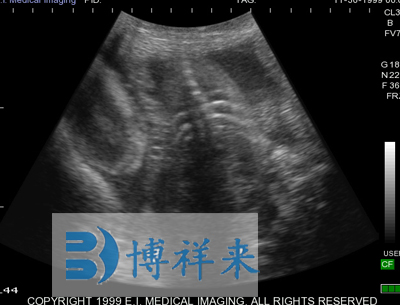

使用对象:牛、马等动物

| 超声类型 | 数字超声 | 产科软件 | 各种动物妊娠期参数表格 |